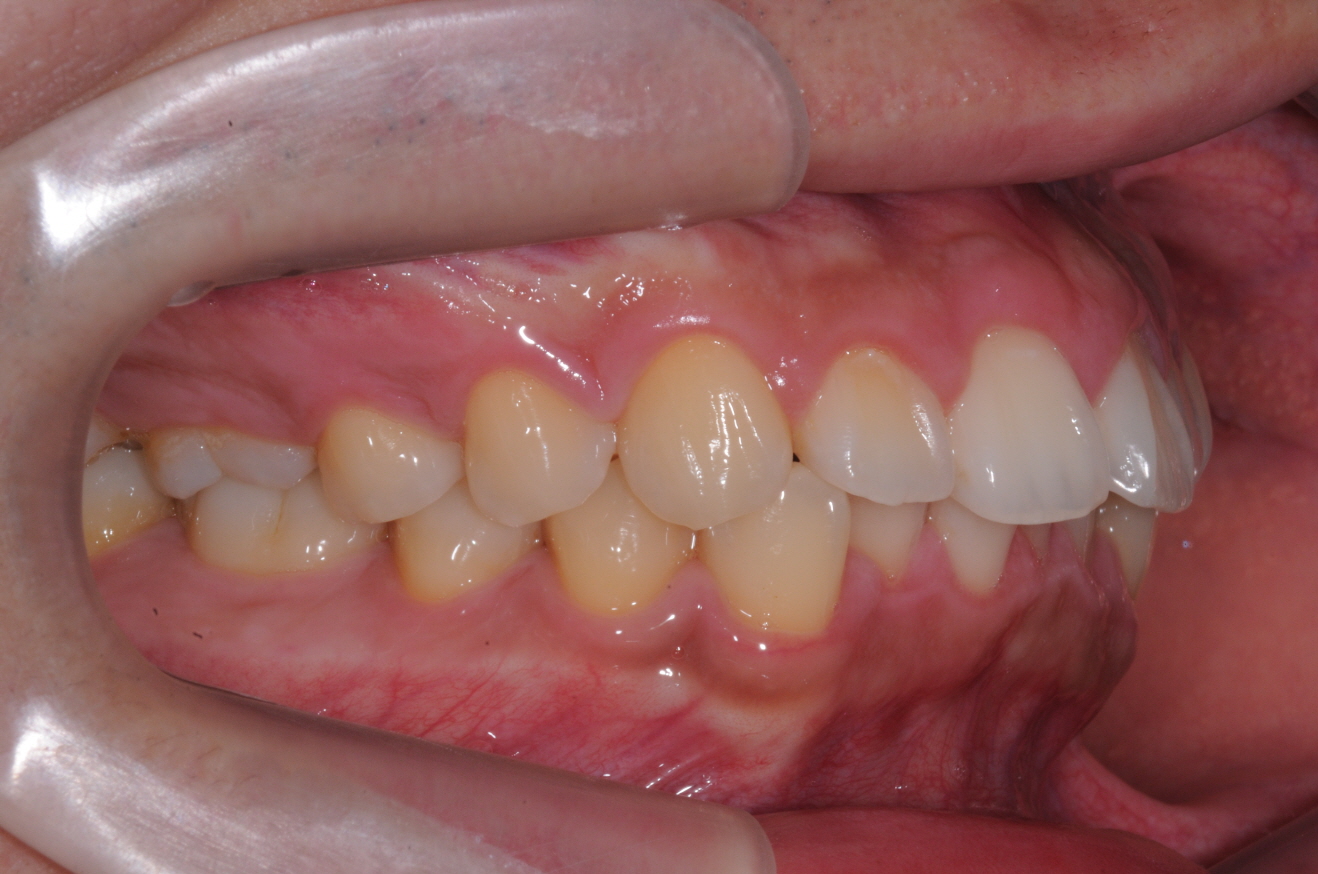

안녕하세요 답변 부탁드립니다.[치아 사진 첨부]

안녕하세요 많은 분들이 질문 남기시는데도 정성스럽게 답변 남겨주시느라 수고가 많으시네요 ㅜㅜ 20대 후반 직장인입니다. 어릴 때부터 교정을 너무 하고 싶었는데 여러 이유로 미루다 이제 정말 더 늦으면 안될 거...